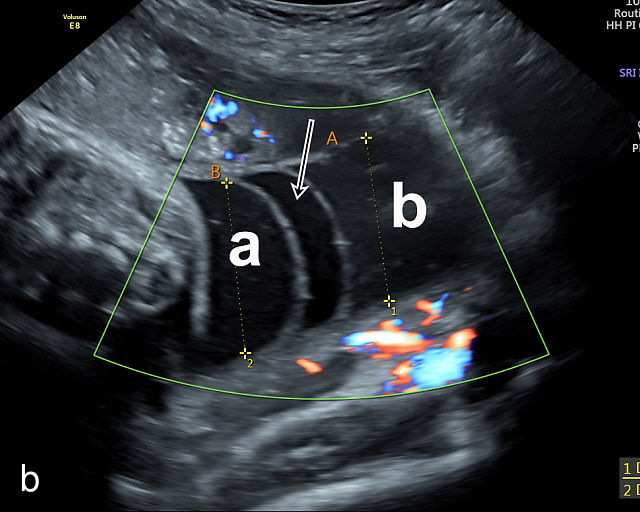

There are three types of vasa previa.30,262 In Type 1, the cord inserts into the membranes rather than the placenta. Unprotected vessels then traverse the membranes over the cervix to insert into the placenta (Figure 21a; Video 12). In Type 2, unprotected vessels running through the membranes over the cervix connect the main placental lobe with an accessory lobe (Figure 21b).263 In Type 3, there is generally a normal placental cord insertion, and unprotected vessels exit one placental edge, run through the membranes over the cervix and then boomerang to insert into the placental edge at another site (Figure 21c).25,28,29,264 Regardless of the type, all these expose the fetus to the same risks.

21